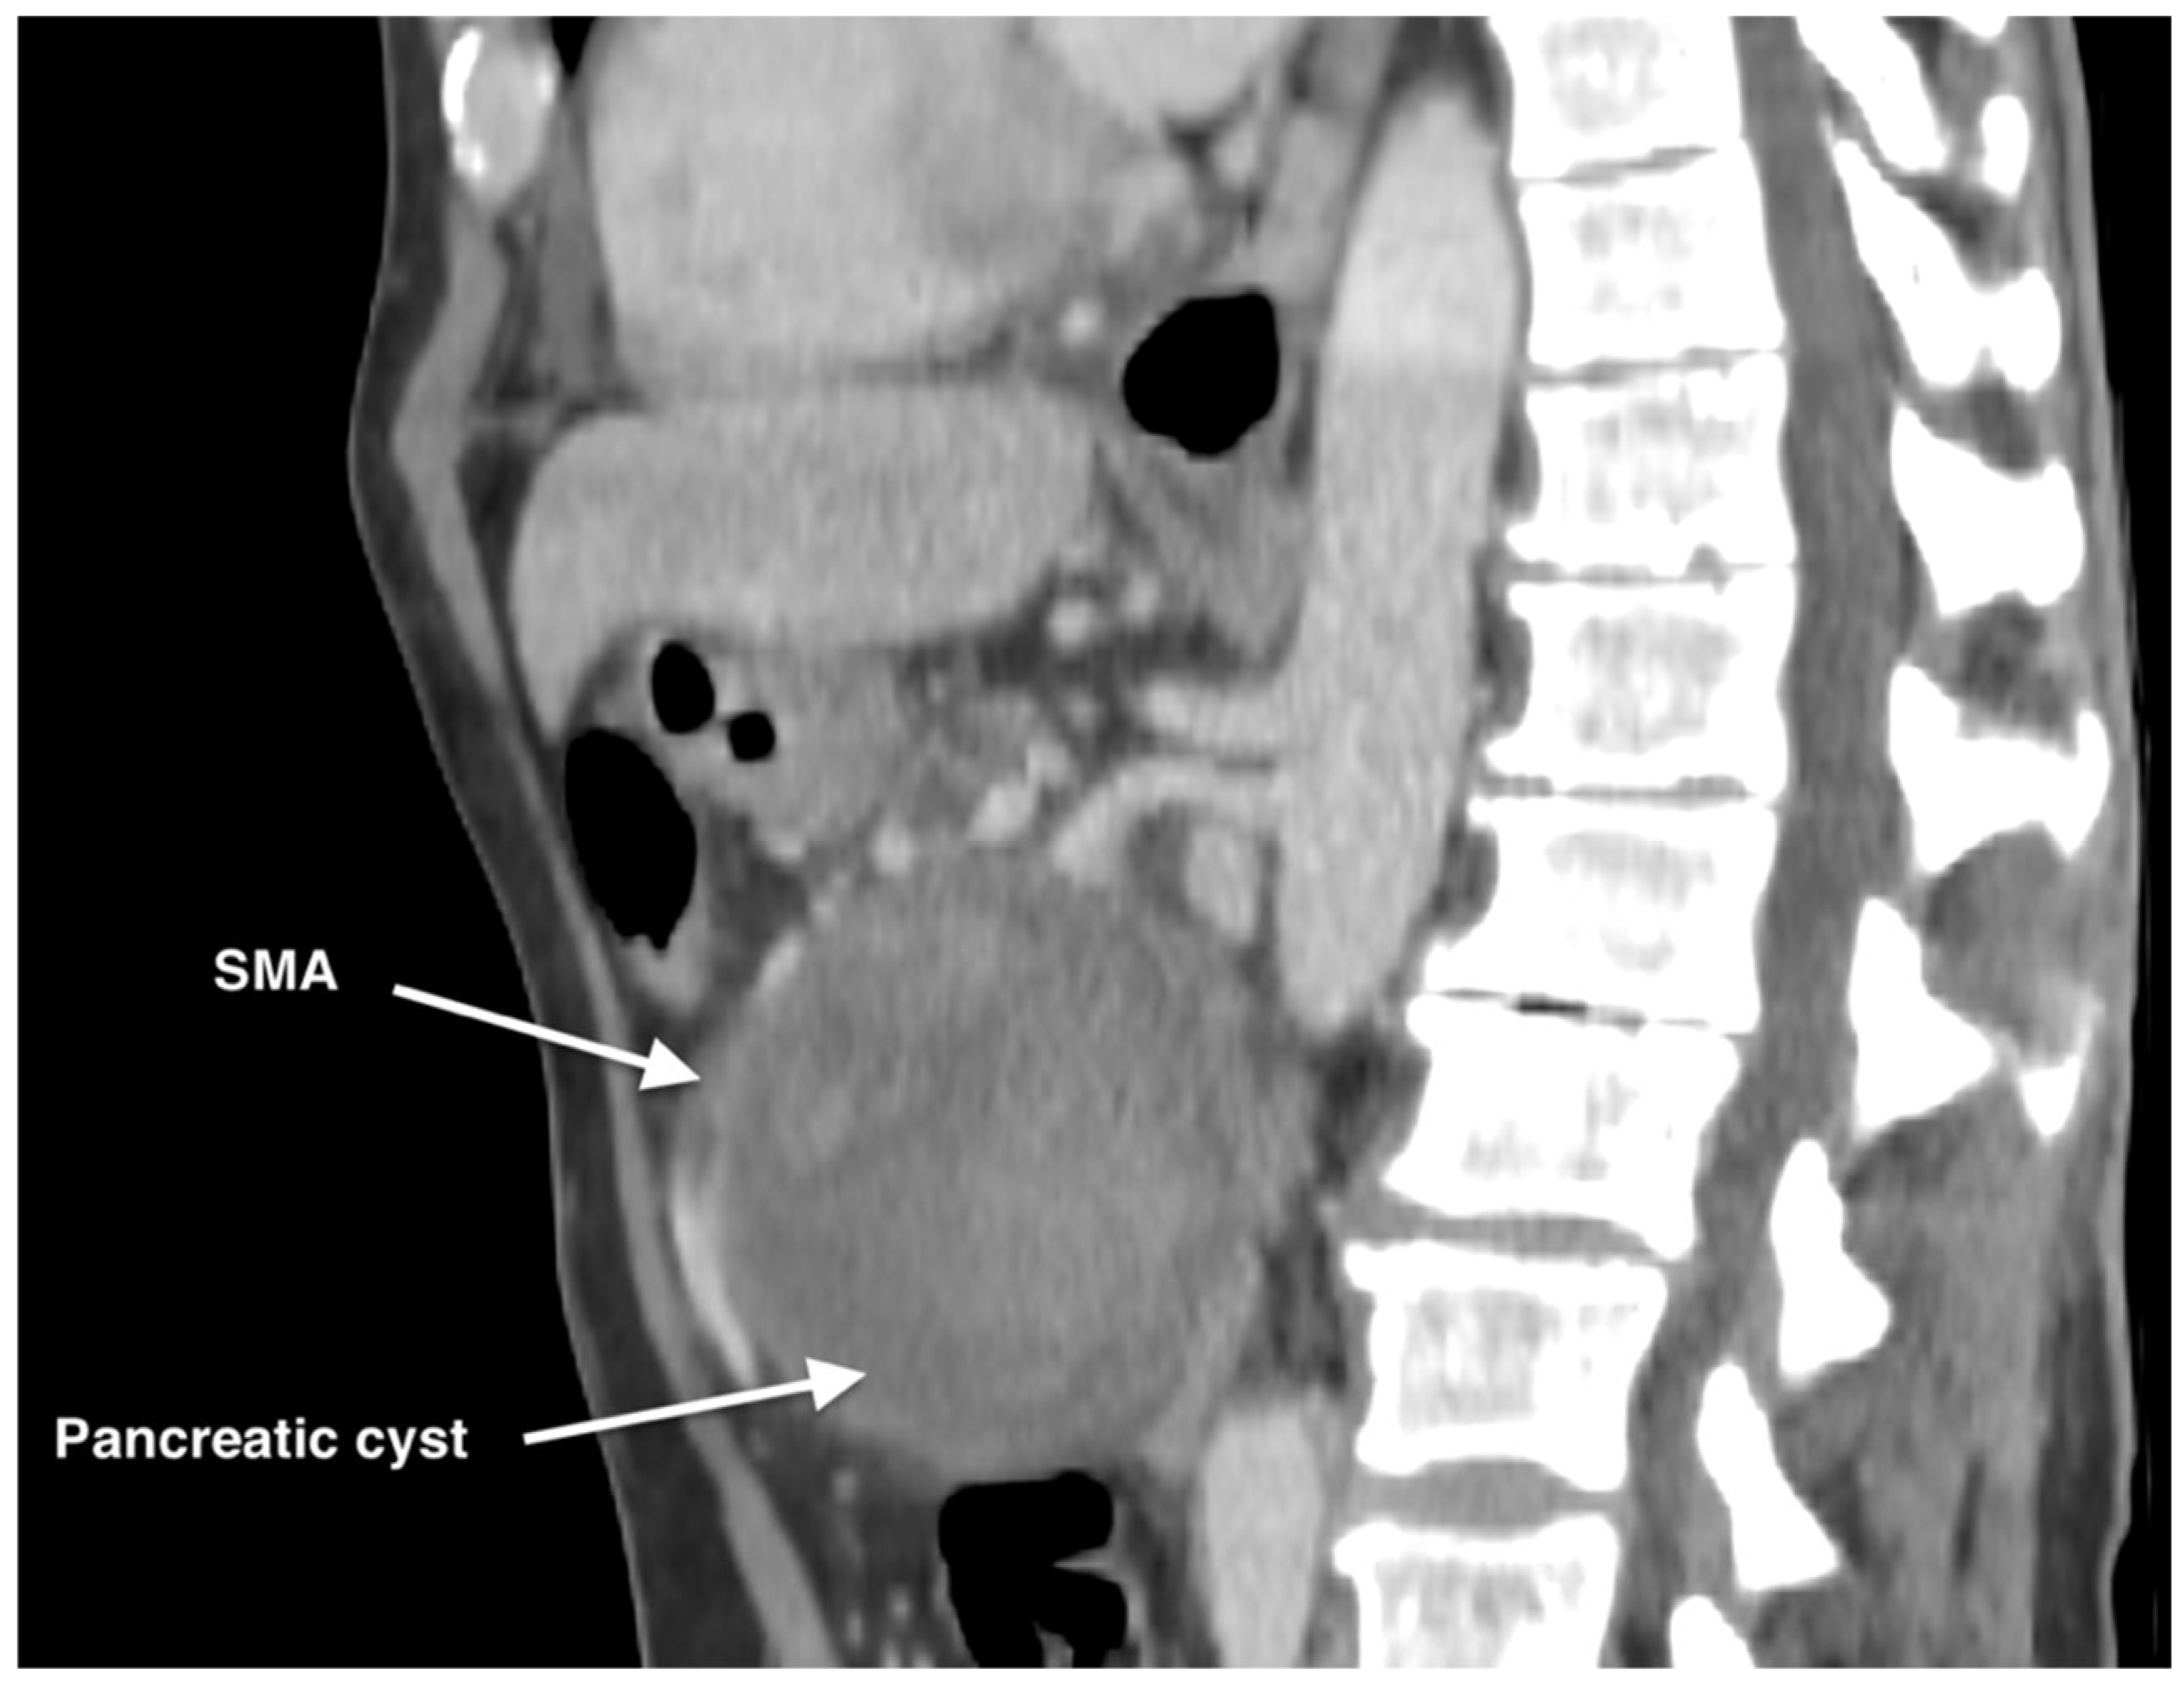

Management of a Rare Case of Superior Mesenteric Artery Aneurysm Associated with a Pancreatic Cyst Complicated by Acute Rupture: A Case Report and Review of Literature

2. Case Report